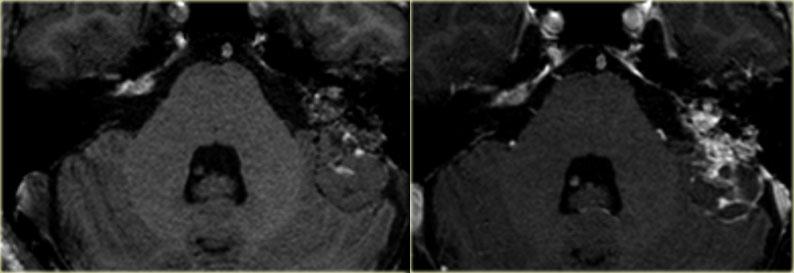

Hình ảnh bên trái của bệnh nhân nam 56 tuổi, là ứng viên cấy ốc tai điện tử.

Vôi hóa nhỏ tại vòng đáy ốc tai là hậu quả của viêm mê đạo xương hóa (mũi tên).

Hình ảnh bên trái của bệnh nhân nam 14 tuổi với điếc tiếp nhận hai bên.

Vôi hóa ống bán khuyên trên bên trái (mũi tên vàng).

Tai phải để so sánh (mũi tên xanh lam).

Hình ảnh mặt phẳng coronal của cùng bệnh nhân trên.